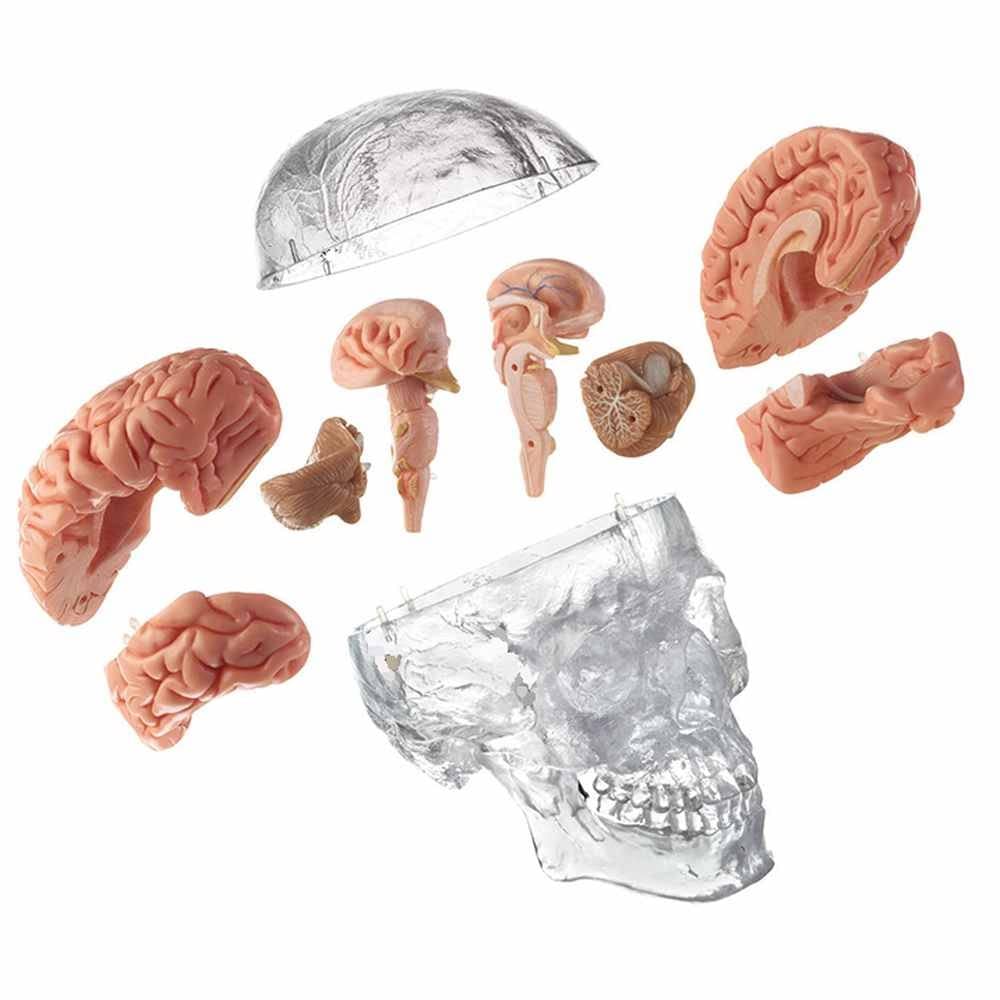

This model is cast from a high-quality original specimen. The classic skull is medically detailed in structure. It has highly accurate representation of the fissures, foramina, processes, sutures etc. Skull is 3-part: Skull Cap, Base of Skull and Mandible. The mandible is articulated on springs to demonstrate natural movements. Use this unique transparent replica of the human skull to study internal structures that otherwise are visible only through x-ray images. Brain separates into 8 parts: frontal and parietal lobes (2), temporal and occipital lobes (2), medulla (2), cerebellum (2). Structures are shown in great detail with about 30 features marked with numbers. Number key is provided. A great addition to any educational collection. Size: Life size Measurement: 22X13X17cm Weight: 2 kgs Material: high quality PVC

- The skull is 3-part: Calvaria, Base of Skull, and Mandible.

- The brain can be disassembled into 8 parts.